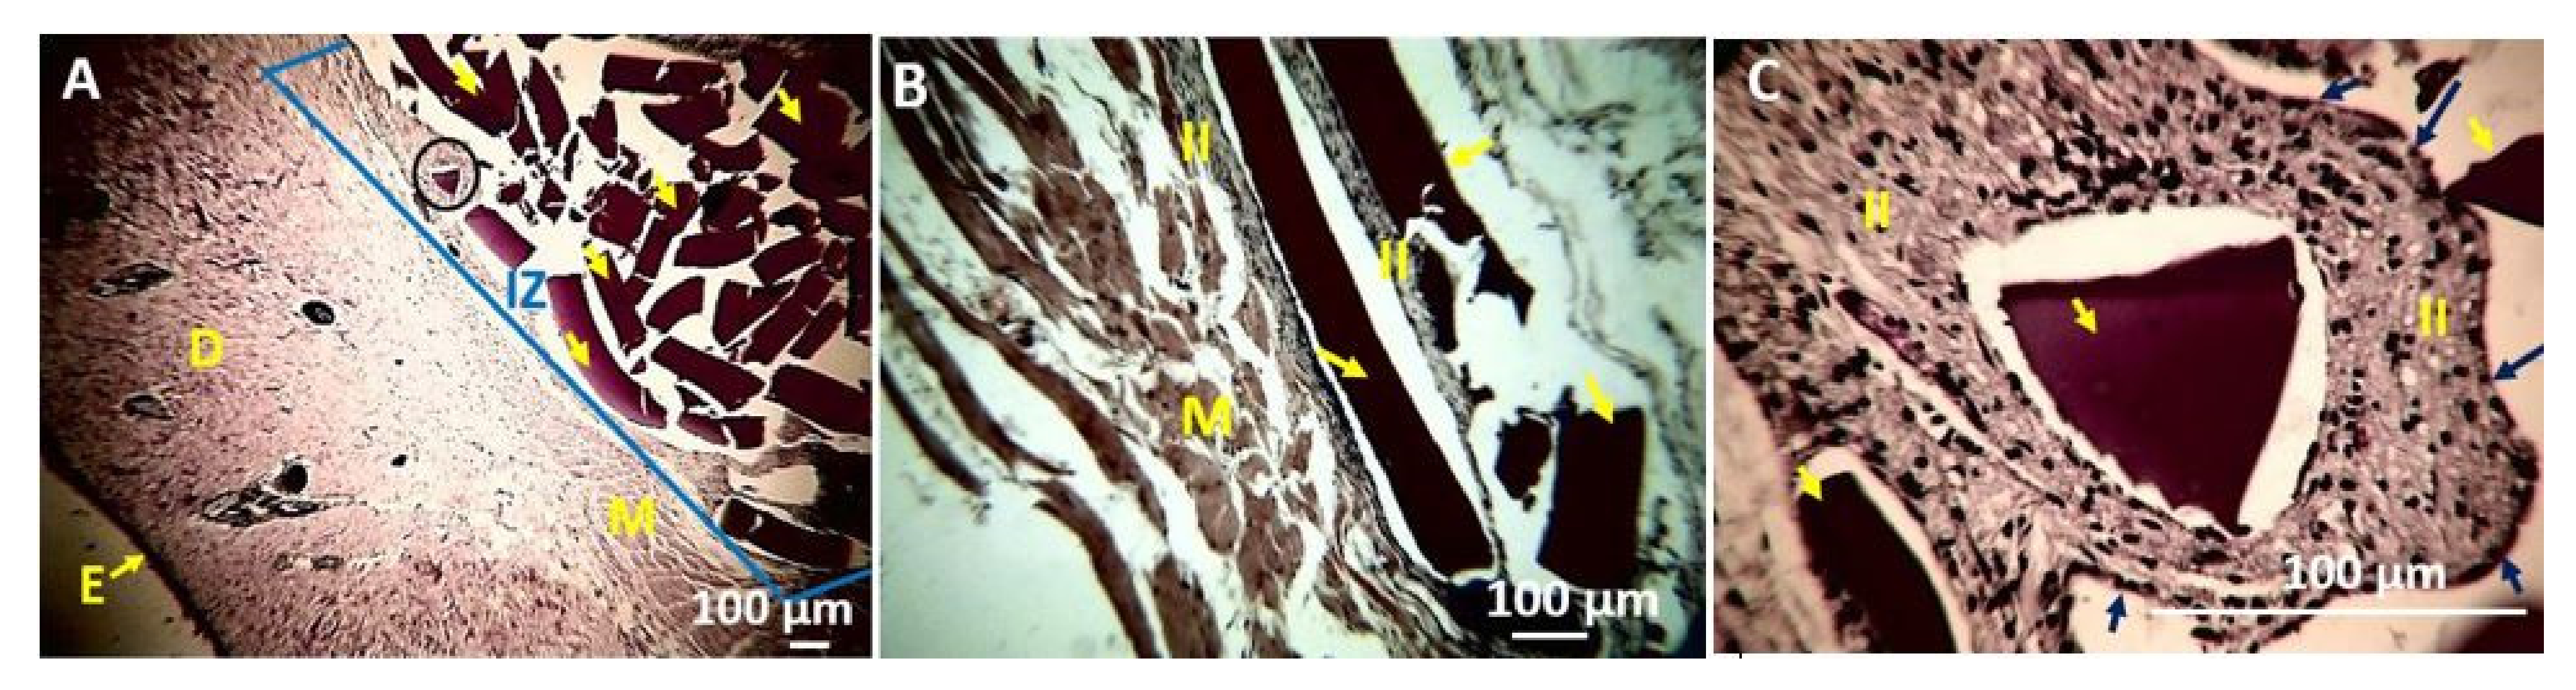

4. In Vivo Biocompatibility Tests of the CS/PVA/TTEO Films